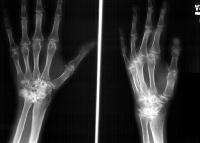

Clinical Example: Rheumatoid arthritis with DRUJ and radiocarpal involvement

Rheumatoid arthritis has many forms of presentation. This patient has bilateral severe radiocarpal and distal radioulnar joint involvement, with relative sparing of the metacarpophalangeal and interphalangeal joints.

The radiolunate joint did not spontaneously fuse on this side, allowing a greater degree of ulnar translation of the carpus. Note the severe cystic carpal changes.